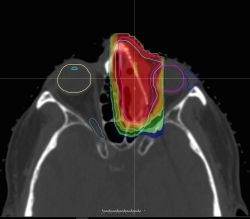

מביון מערכות רפואיות (Mevion Medical Systems) קיבלה אישור 510(k) מה-FDA עבור MEVION S250i Proton Therapy System® כולל טכנולוגיית ה-